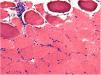

The biopsy of the vastus lateralis muscle was performed in May 2016 and demonstrated small vessel vasculitis, perimysial fibrosis, and scattered atrophic muscle fibers (Figure 1). It showed no evidence of muscle fiber necrosis or inclusion body formation. There was a mixed inflammatory infiltrate of CD3-positive T cells and plasma cells. Immunohistochemical staining for T cells demonstrated lymphocytic infiltration of the perimysial arterial wall (Figure 2). The pathology findings were considered consistent with chronic GVHD-associated inflammatory myopathy. Based on these findings, prednisone was increased to 50mg daily and weekly extracorporeal photopheresis (ECP) treatment was initiated. Monthly treatment with IVIG 40g for chronic GVHD was also started in September 2016, an increase from his 15g dose in June 2016. Due to a lack of symptom improvement, ibrutinib 140mg daily was added in November 2016 and subsequently increased to 320mg daily. The IVIG and ECP treatment was discontinued in December 2016 due to insurance changes for the patient.

Muscle biopsy of left vastus lateralis performed during his hospitalization revealed prominent variation in the size of the few myofibers identified, some with internalized nuclei. Atrophic fibers were seen isolated or in groups, with rare regenerative fibers noted. Histochemical trichrome stain did not reveal the presence of ragged red fibers or rimmed vacuoles. There was increased connective tissue, within the perimysium and endomysium, with presence of abundant adipose tissue surrounding the few surviving fibers. The pathology was consistent with inflammatory myopathy related to chronic GVHD.